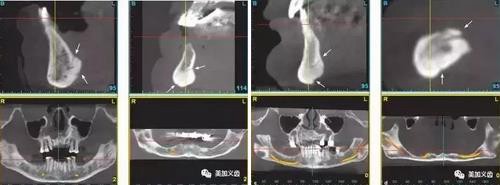

5、術(shù)前一定要拍CT,研究植入位點解剖結(jié)構(gòu)。

1、舌下動脈分支可通過副舌孔進入前磨牙或前牙區(qū)下頜骨(中線處較多見)。

4、無牙頜患者牙槽骨嚴(yán)重吸收者,舌頦動脈離牙槽嵴頂近,種植體植入易傷及舌頦動脈。